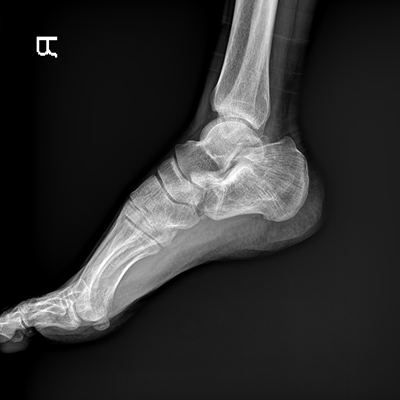

●探測器可以大范圍轉動,大尺寸有效探測面積,可滿足人體多部位攝影需求。

● 自主研發大功率高頻高壓發生器,性能更優。

● 支持kV. mAs兩鈕制、kV. mA. s三鈕制及AEC自動曝光三種攝影模式,能更好的滿足不同用戶的使用需求。